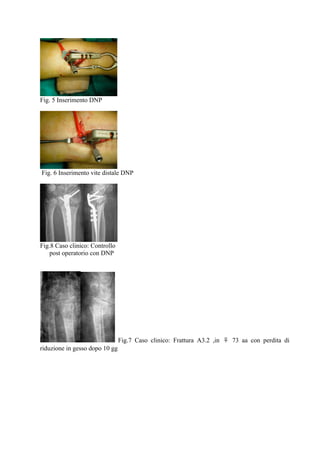

Fig. 5 Inserimento DNP

Fig. 6 Inserimento vite distale DNP

Fig.8 Caso clinico: Controllo

post operatorio con DNP

Fig.7 Caso clinico: Frattura A3.2 ,in ♀ 73 aa con perdita di

riduzione in gesso dopo 10 gg